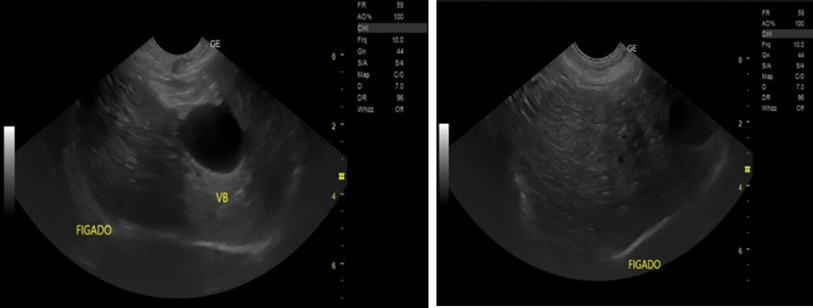

Acute Acalculous Cholecystitis Associated with Severe Malaria – A Case Report

Teresa Oliveira, Ana Clara Dinis, Sofia Narciso, Tiago Pereira, Nuno Catorze